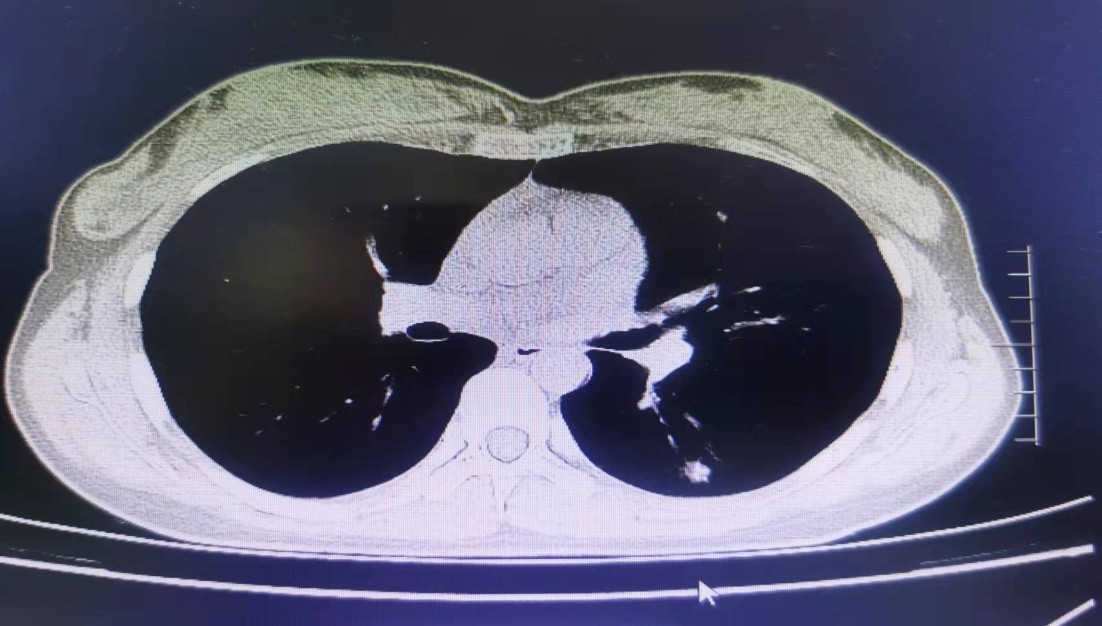

病例二:张X,女,27岁,未婚,体检发现左下肺结节半天就诊于 2022年6月28日 。查体:生命体征正常,一般良好。锁骨上的淋巴结不大。胸部CT见左肺下叶背段结节,大小约1cm*0.8cm,内见支气管截断样改变(见图),经过几位专家仔细认真讨论,认为该病人感染性病变可能性大,建议行抗炎治疗1-2周后再行复查。

该病人经抗炎治疗后结节明显缩小,考虑炎症的可能性大。